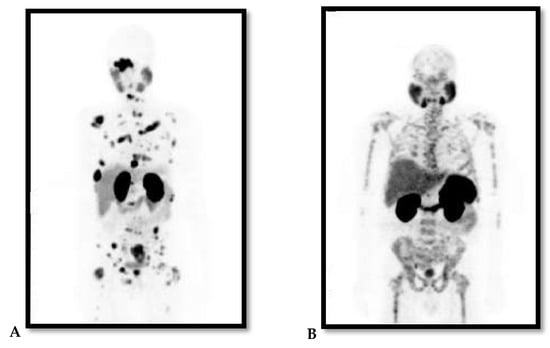

| SASCRO/SASMO CONFERENCE ORAL PRESENTATION (BOSHOMANE ET AL., 2016-UNPUBLISHED DATA) | Prospective | • Response & safety | • No side-effects & adverse presented | • Demonstrated favourable response, i.e., no lesions and also a decrease in sPSA levels. |